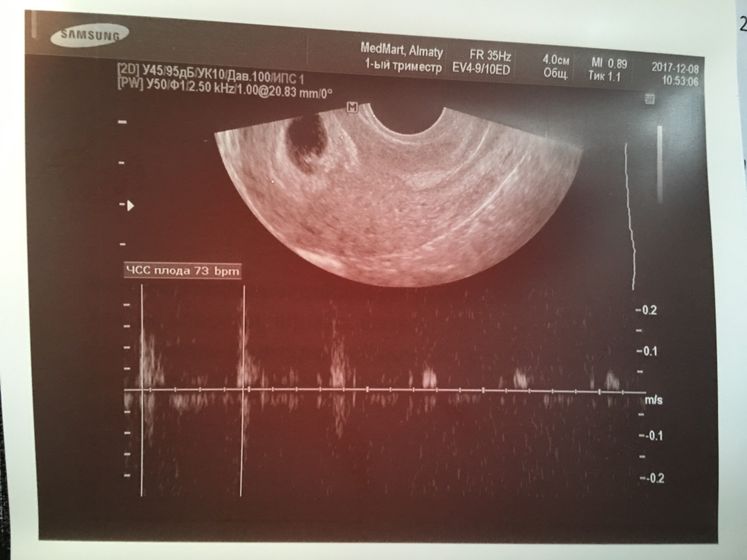

ЧСС плода 73.

Сказала главное сердцебиение есть, какие говорит врачи смотрели, раз не могли просто посчитать и написали просто слабо положительное. Всегда надо считать.

А где вы находитесь? Где такие врачи некомпетентные? 73 сб маловато тоже. Но дай Бог, все будет хорошо! Удачи вам

Я в Казахстане, в Алматы. Гинеколог мой говорит, у тебя 4 недели и сердцебиение в норме. Меньше ходите к врачам некомпетентным сказала.